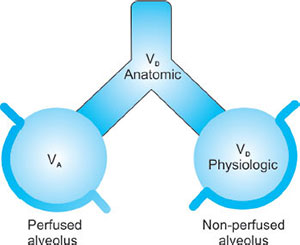

DEAD SPACE

- Anatomical dead space: This includes any breathing system or airway plus mouth, trachea and the airways up until the start of the respiratory zone—does not take part in air exchange.The typical volume in an adult is about 150 mL.

- Alveolar dead space: This occurs when areas of the lung are being ventilated but not being perfused and this leads to what is known as V/Q mismatch.25Large increases in alveolar dead space commonly occur in the following conditions: pneumonia, pulmonary edema, and pulmonary embolism

- Physiological dead space = alveolar + anatomical dead space.Dead space is usually 30% of VT.